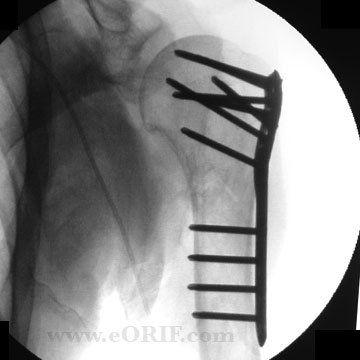

Conditions Mr Treseder treats frequently include fractures and dislocations of the upper limb and lower limb, deformity correction, joint problems and arthritis.

elbow fracture dislocation protocol

elbow reconstruction protocol